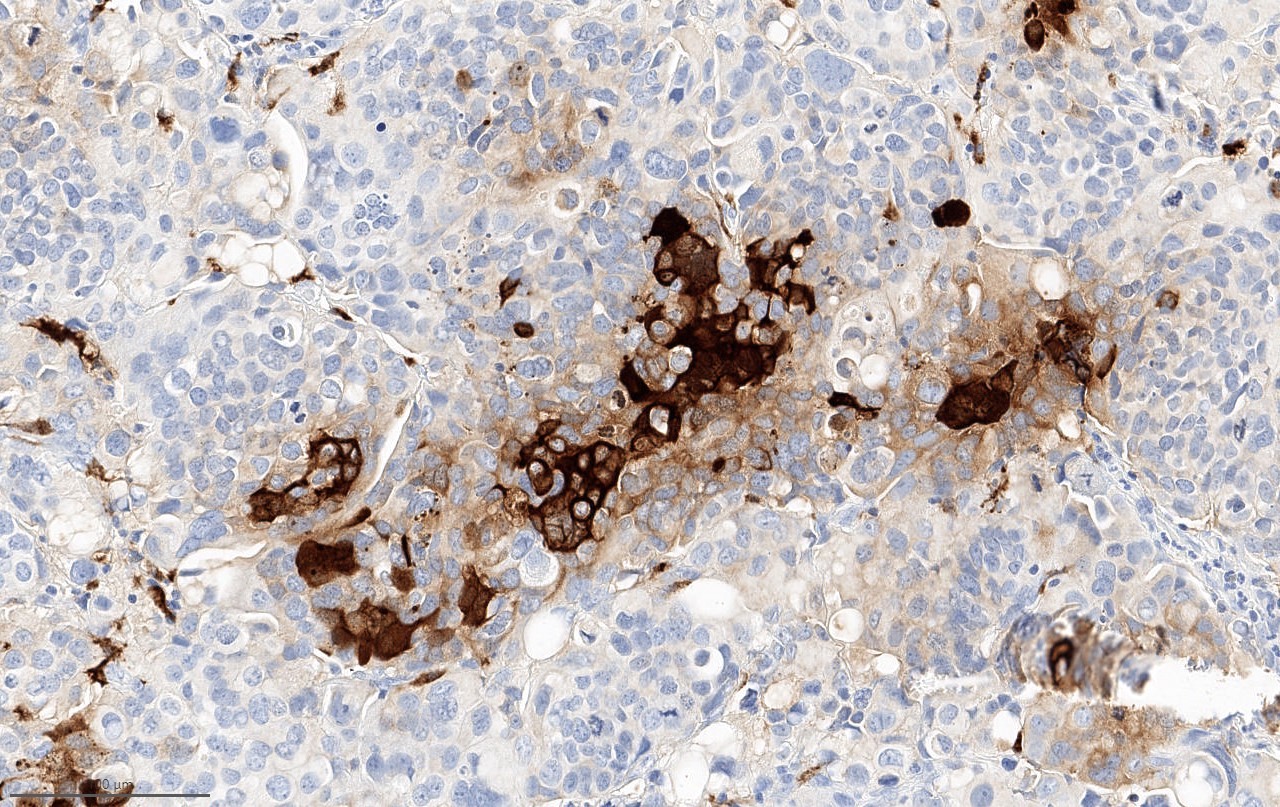

- Beta hCG immunohistochemical stain highlights cells with trophoblastic differentiation

Microscopic (histologic) images

Positive stains

- Beta hCG: syncytiotrophoblasts and intermediate trophoblasts

- GATA3 and HSD3B1 (Am J Surg Pathol 2020;44:1322)

- Comment: Muscularis propria is identified and is non-involved. Immunohistochemical studies reveal that a subset of tumor cells are positive for beta hCG and GATA3 supporting the presence of trophoblastic differentiation.